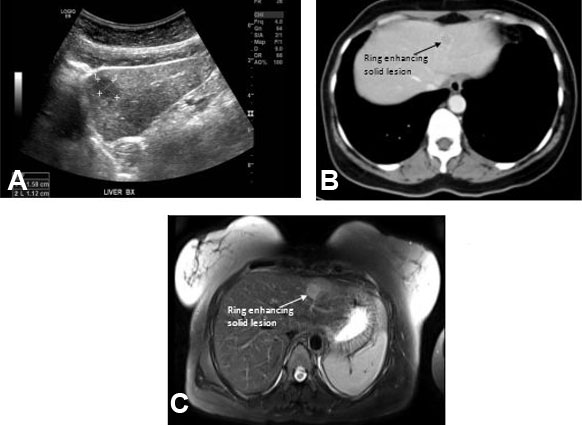

Although SARS-CoV-2 is a new virus, it belongs to the family of corona viruses and shares some common features with the other family members. Concerning the symptoms of a COVID-19 infection, it resembles those of other respiratory pathogens like influenza virus. To assess cross reactivity the batches were tested against antigens of several respiratory viruses, i.e., different respiratory pathogens as well as the different available SARS-CoV-2 antigens (Figure 3).

Two pre-pandemic batches showed very low signal against all SARS-CoV-2, SARS-CoV, and MERS antigens. This was expected and judged as background signal or natural cross reactivity. Interestingly all batches showed very comparable high-level activity against the circulating corona viruses and influenza. This shows the high prevalence of these viruses in the population as well as the very low cross reactivity between these viruses and the corona viruses causing severe respiratory syndromes (SARS-CoV-2, SARS-CoV, MERS).

Intravenous immunoglobulins from convalescent as well as vaccinated donors showed high reactivity against the spike proteins of Corona viruses causing severe respiratory syndromes. The preparations from vaccinated individuals showed in general a lower reactivity against the SARS-CoV-2 nucleocapsid antigen since the majority of vaccines distributed in the United States and Europe are based on the SARS-CoV-2 spike protein only. Early batches from 2021 showed very low activity against SARS-CoV-2 in the ELISA test, whereas the activity in later batches rose with one batch close to the reference of convalescent donors (Figure 3).

Figure 3: Activity against different antigens of respiratory viruses. Signal of different samples (n=11 batches produced in 2021) against antigens from different Corona viruses and an influenza strain, details are listed in Method section. Antibody preparations solely made from convalescent donors (n > 1000 donors) or vaccinated donors (n=2 donors), respectively as well as two pre-pandemic batches (produced in 2017) are added as reference. CoV = Corona virus; MERS = Middle East respiratory syndrome; S = Spike protein, NTD = N terminal domain (of the Spike protein); RBD = Receptor binding domain (of the Spike protein); H3/Hong Kong = Influenza virus strain; HKU1 = Corona virus strain; OC43 = Corona virus strain.